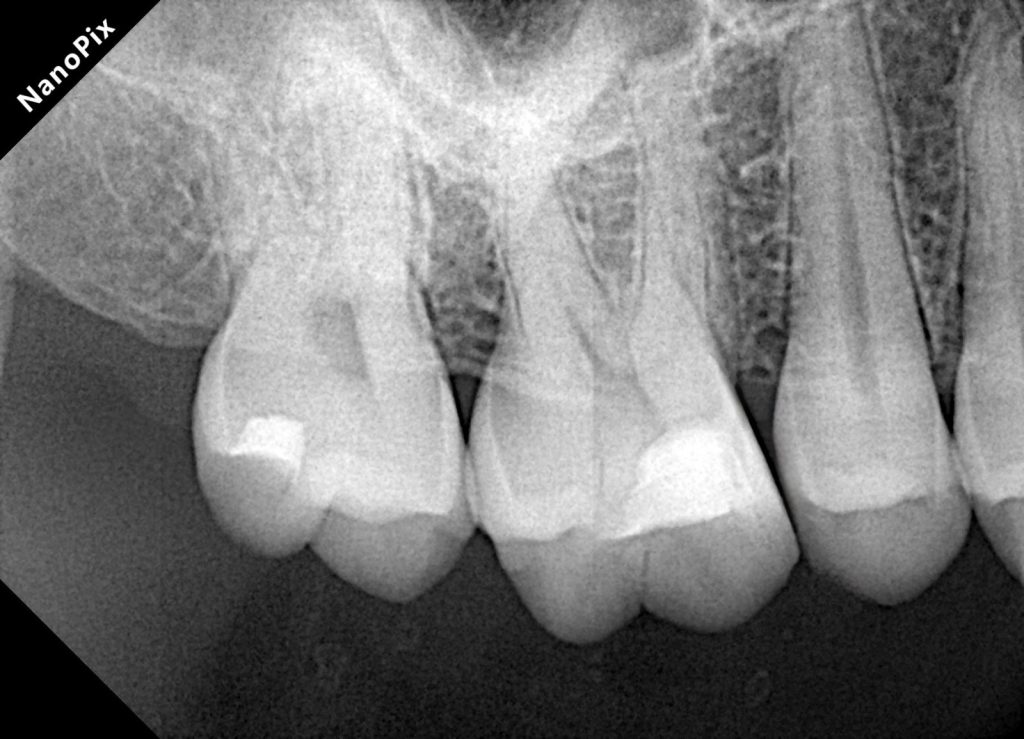

Bitewing radiographs show a small proximal radiolucency without pulpal involvement.

→ Perfect indication for a conservative Zerodont restoration.